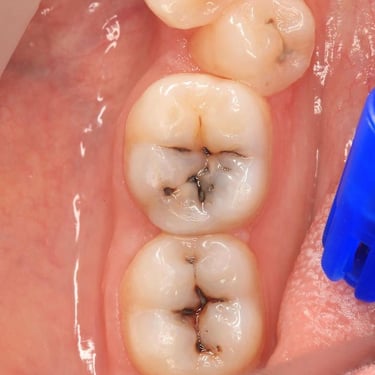

COMPOSITE FILLINGS

Dental fillings are materials used to repair cavities and restore damaged teeth, preventing further decay and restoring tooth function and shape.